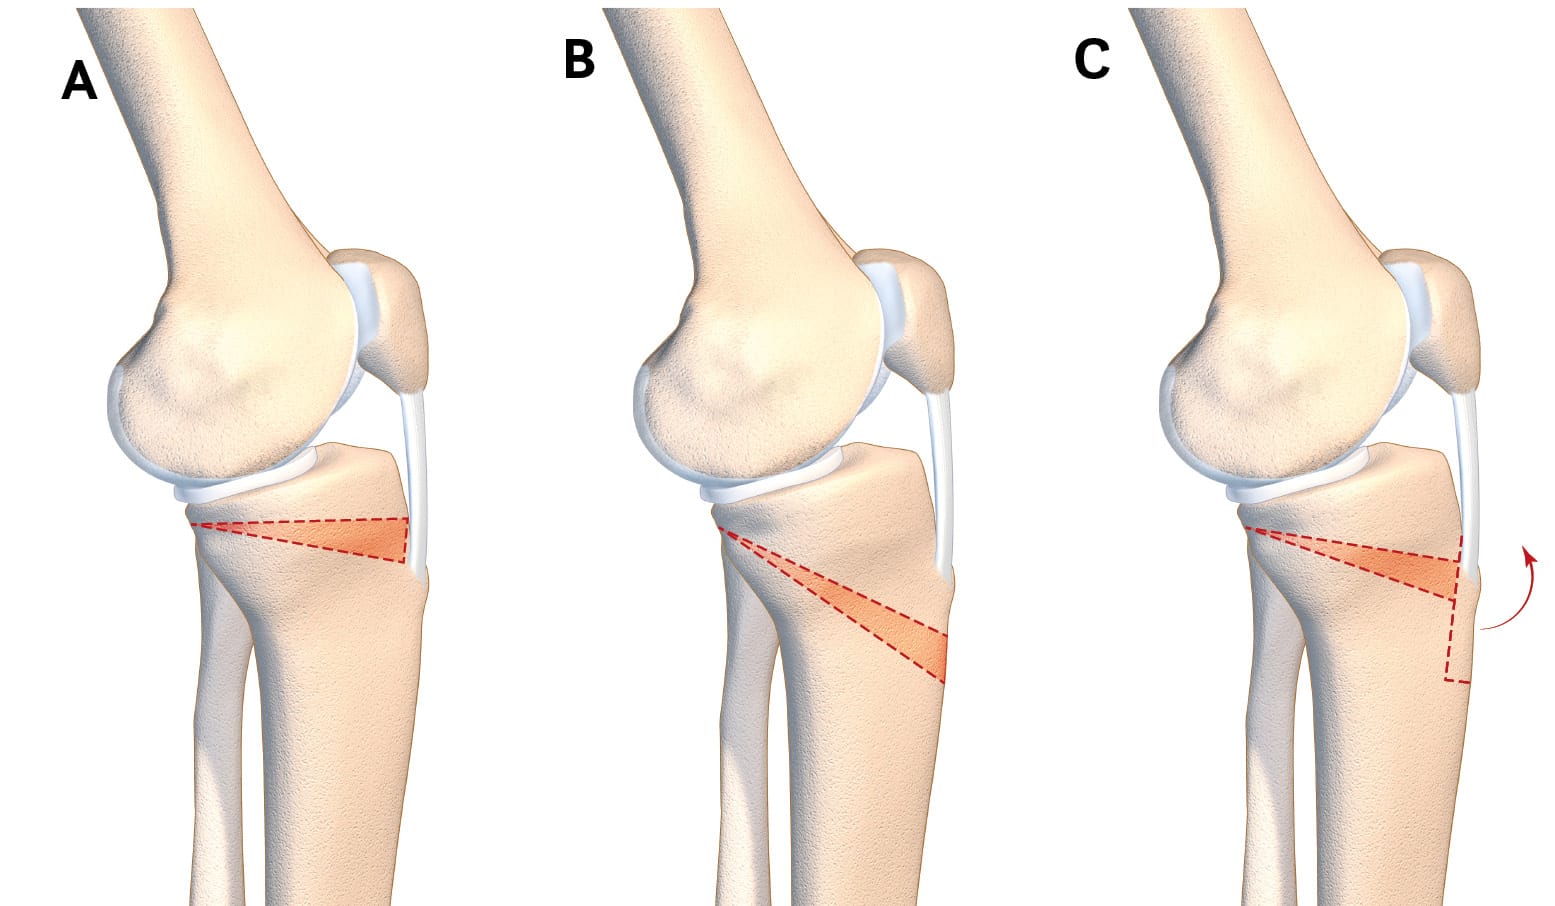

The intervention that directly addresses tibial slope is the tibial deflexion osteotomy (TDO) [18] Guarino A, Pineda T, Giovannetti de Sanctis E, van Rooij F, Saffarini M, Dejour D. The Original Technique for Tibial Deflexion Osteotomy During Revision Anterior Cruciate Ligament Reconstruction: Surgical Technique. Arthroscopy Techniques. 2024 Jan 1;13(1):102824. . This intervention was notably described by Dejour et al. in 1998, although it has been discussed at the Lyon Knee Surgery Congress since the early 1990s [19], Dejour D, Kuhn A, Dejour H. Osteotomie tibiale de déflexion et laxité chronique antérieure à propos de 22 cas. Rev Chir Orthop 1998 ; 84 SII : 28-29 [20] 7èmes journées lyonnaises de chirurgie du genou - Lyon 1991 [Internet]. [cited 2024 Aug 23]. Available from: http://lyon-knee-surgery.com/images/pdf/7%C3%A8mes%20journ%C3%A9es%20lyonnaises%20de%20chirurgie%20du%20genou%20-%20Lyon%201991/jdg-7/assets/basic-html/page-270.html. It is a sagittal realignment osteotomy. The technique described here is a supra-tubercular osteotomy (Figure 4). However, trans-tubercle and infra-tubercle strategies are also possible (Figure 5). This intervention is performed at the same time as the ACL reconstruction.

The procedure to choose to directly address posterior tibial slope is tibial deflexion osteotomy. It is possible to perform a supra-tubercular, trans-tubercle or infra-tubercle deflexion osteotomy, as described above (Figure 7). The most important factor in choosing a technique is that the surgeon feels at ease using it, since there is currently no technique emerging as superior to any other and each one has its own advantages and drawbacks [29] Onishi S, Kim Y, Nakayama H, Mansour AA, Lowe WR, Ollivier M. Infratubercle Anterior Closing Wedge Osteotomy Corrects Sagittal Alignment without Affecting Coronal Alignment or Patellar Height. Journal of Clinical Medicine. 2024 Jan;13(16):4715. . We have set out the technique for the supra-tubercular osteotomy because this technique means that the resection can be made at the site of the deformity, in the metaphysis, in an area that is favourable to bone healing [30] Demey G, Giovannetti de Sanctis E, Mesnard G, Müller JH, Saffarini M, Dejour DH. Posterior tibial slope correlated with metaphyseal inclination more than metaphyseal height. Knee. 2023 Oct 1;44:262–9. . It has been clearly demonstrated that this osteotomy technique preserves sufficient metaphyseal bone for fixation [31] Demey G, Giovannetti de Sanctis E, Mesnard G, Müller JH, Saffarini M, Dejour DH. Sufficient Metaphyseal Bone for Wedge Removal and Fixation Hardware During Supratuberosity Tibial Deflexion Osteotomy in Knees With Excessive Posterior Tibial Slope. Am J Sports Med. 2023 Jul 1;51(8):2091–7. . The goal of this surgery is to obtain a tibial slope of between 4 and 6°, which means that SATT will be kept between 0 and 5mm without increasing the stresses on the posterior cruciate ligament (Figure 8).